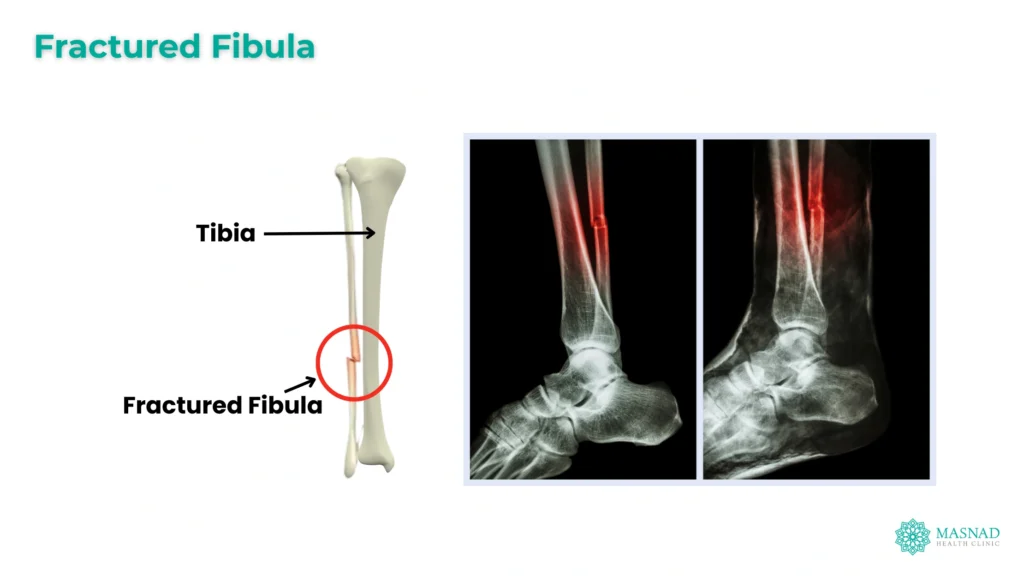

A fibula fracture is a break or crack in the fibula, the smaller of the two bones in your lower leg, located alongside the tibia. While the tibia bears most of your body weight, the fibula is important for stability of the ankle and supporting muscles of the lower leg.